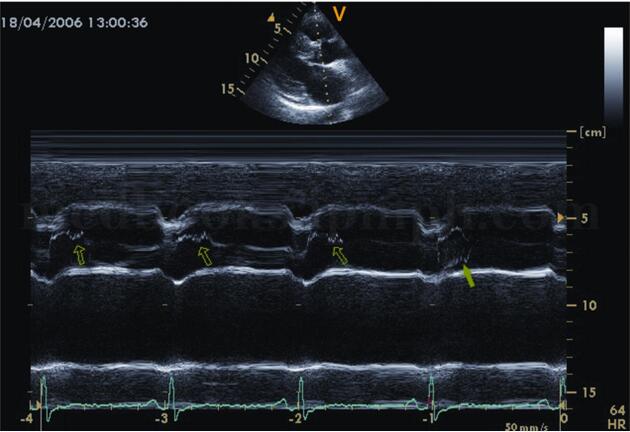

(1)梗阻者二尖瓣C‐D段呈多层弓背样隆起,称为SAM现象(systolic anterior mo tion,SAM)(图2‐1‐204)。

(2)二尖瓣EF下降速率减慢,二尖瓣前叶舒张期开放时E峰常与室间隔相撞(图2‐1‐205)。

(3)肥厚的室间隔突入左室流出道致其狭窄,正常左室流出道内径为20~40mm,梗阻时<20mm。

(4)主动脉瓣收缩中期提前关闭,出现收缩期半关闭切迹,右冠瓣呈“M”形,无冠瓣呈“W”形(图2‐1‐206)。

(5)肥厚的室间隔收缩运动呈低平状,左室后壁收缩运动增强。早、中期左室收缩功能正常或增强。晚期收缩功能下降。